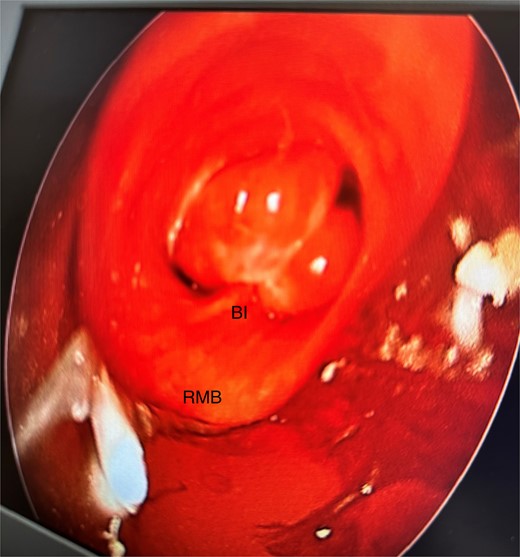

Anomalous right bronchial anatomy was also noted (Fig. 3). The biopsy was sent for frozen section, which confirmed a carcinoid tumour.

Post disobliteration of the tumour through rigid bronchoscopy, also showing aberrant anatomy, where the apical segmental bronchus of the right upper lobe has a high take off at the distal trachea/carina; C, carina; RMB, right main bronchus; BI bronchus intermedius; RULB, right upper lobe bronchus; ASB, apical segmental bronchus.